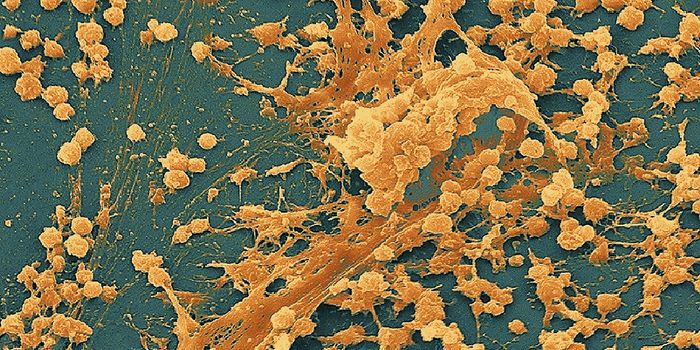

JUL 09, 2015MicrobiologyBiofilms consist of surface-associated bacteria surrounded by an extracellular matrix (think dental plaque). Biofilms of ...

-

OCT 30, 2015MicrobiologyStaphylococcus aureus is notorious for forming biofilms on indwelling medical devices (things like urinary and vascular ...

-